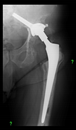

The direction of the cup stem was determined by the guide wire. The aiming device was needed to introduce this wire. After removing the aiming device, the next step was the drilling. Since a cannulated drill bit was used, the previously installed wire could guide the process. A self-positioning reaming tool was then used in the drilled channel. In the prepared cavity, the cup was fitted perfectly. Of the two stemmed cups available to us, the McMinn cup (Waldemar Link, Hamburg, Germany) had the simpler geometry and was therefore chosen. The stemmed cup was inserted according to the manufacturer’s recommendation. In the presence of a significant bone defect, a synthetic bone graft may be impacted for substitution.

The radiological examination allowed us to verify the close bone-to-implant contact and the unchanged position of the implant during follow-up.

In all the cases operated with the above-described targeting procedure, the stems of the cups remained between the cortical bone surfaces without perforation of the linea terminalis, as shown by postoperative radiographs. There were no complicated surgical situations. In 16 cases, the wound healings were uneventful, and the hips were able to bear weight again after postoperative rehabilitation.